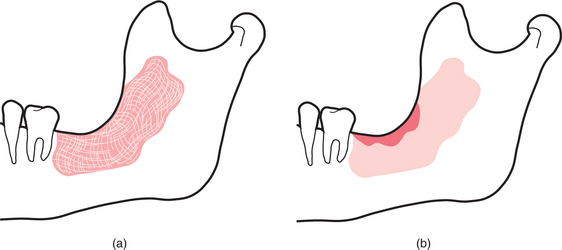

Marsupialization

Marsupialization involves the surgical excision of the superficial part of the cyst lining to convert the cavity into a pouch (Fig. 9.7). It is based on the principle that cysts will shrink to smaller more manageable size when decompressed. In some cases this process continues and the lesion resolves completely without further intervention but many require secondary surgery to remove the residual lining.

image

Fig. 9.7 (a) Marsupialization followed by packing of the cavity. (b) After a period of months the cavity has reduced in size; enucleation at this stage would be a much smaller operation.

Indications

It is an ideal treatment when the cyst is large and the resultant defect from enucleation would be too large to heal by primary intention or may even require bone grafting; similarly so for infected cysts, where primary closure of the wound would not be an option. The technique also minimizes the potential for damage to adjacent structures, such as the inferior alveolar nerve during the enucleation of large cysts at the angle of the mandible, or the apices of vital teeth where the cyst extends up around them. As it can be done under local anaesthetic it is suitable for treating large lesions in elderly patients or those with major co-morbidity, thus avoiding a major procedure and a general anaesthetic. In addition, as marsupialization involves the excision of the superficial portion of the cyst lining it will establish a histological diagnosis that will determine treatment. This will also prevent more significant lesions such as ameloblastomas being enucleated rather that resected. The main drawbacks are that although the primary procedure is relatively simple there is a protracted follow-up treatment with multiple pack changes.